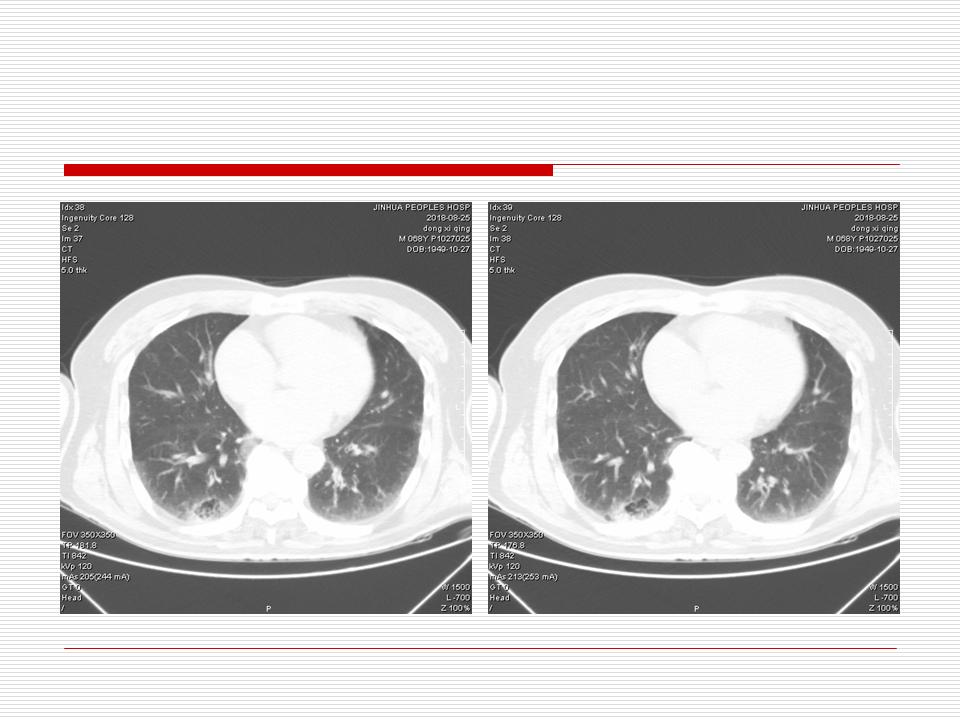

肺部阴影永恒且最重需要鉴别的是:到底是炎症还是肿瘤?但临床的病例中的影像表现难以界定或有些肿瘤特征,同时又有些炎症特点是非常常见的情况。作为临床医生我们怎么去总结分析,并找到之所以是炎症或之所以是肿瘤的细微差别或特点非常重要,也非常有用。2019.12.7浙江省2019年胸心外科学学术年会在宁波召开时,我的临床病例分析与经验总结<那些像肺癌的炎症与像炎症的肺癌>获得在大会交流的机会,以下为该PPT的内容,与你分享,希望对同道有益,有借鉴与启迪。若有探讨与进一不完善的建议,欢迎文末留言讨论: